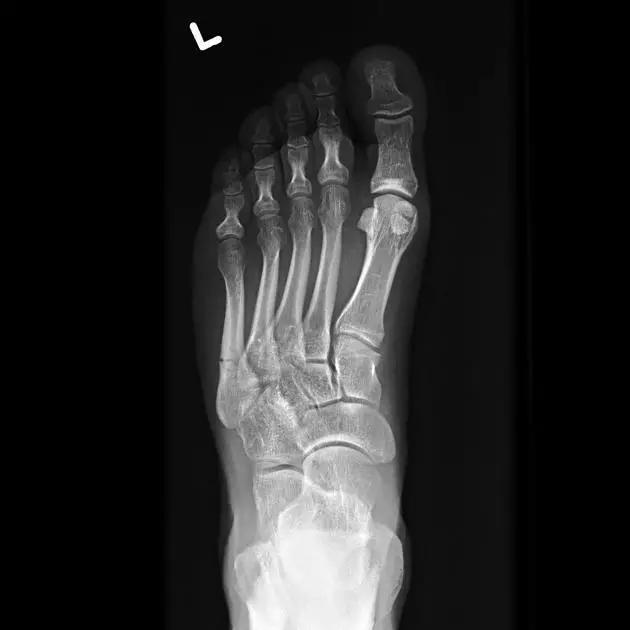

13. Lisfranc 骨折

骨折累及到足的跗骨关节。跖跗关节位于足的前部,是构成足纵弓及横弓的重要结构。

第一跖骨与第一楔骨组成鞍状关节,整个跖跗关节的稳定性,有赖于第一跖跗关节的稳定性,一旦第一跖跗关节发生脱位,其他 4 个跖跗关节容易发生脱位。第一跖跗关节的关节囊有背侧和跖侧副韧带增强,其内缘尚有胫前肌腱附着。第一、二跖骨基部无韧带相连,第一楔骨与第二跖骨基部间有坚韧的 Lisfranc 韧带相连,有助于第一跖跗关节的稳定性。第二楔骨较短,第二跖骨位于第一、二楔骨之间成为外力作用的支点。因此第二跖骨基底易发生骨折。

Lisfranc 关节复合体(Lisfranc joint complex)示意图:first metatarsal 第一跖骨;second metatarsal 第二跖骨;Lisfranc joint 利斯弗朗关节;first,second and third cuneiforms 第一,二,三楔骨;cuboid 骰骨

14.第五跖骨骨折

第五跖骨基底部骨折的不同类型:Stress 骨折;Jones 骨折:第五跖骨基底部以远 1 英寸内的骨折称为 Jones 骨折; Avulsion 骨折。

(来源:Radiopaedia)

Stress 骨折(来源:OrthoInfo-AAOS)

Jones 骨折正位片(来源:Radiopaedia)

Jones 骨折斜位片(来源:Radiopaedia)

第五跖骨骨折还有 dancer’s fracture。

dancer’s fracture 正位片(来源:footEducation)

dancer’s fracture 侧位片(来源:footEducation)